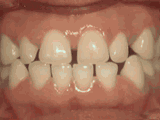

爱美之心,人皆有之~~5月份世界正畸日即将来临,暑假还远吗?分院提前给爱美的你准备好一份大大的福利,还等什么呢?抓紧约起来吧! 发现自己牙齿不整齐影响交际, 怎么还能与小伙伴愉快地玩耍? 无论是即将迈入新的年级还是即将面临找工作, 发现自己是“地包天”“龅牙妹”, 分分钟拉远自己和同龄人的距离! 这些难以启齿的牙齿问题, 想想就让人心碎,怎么办呢? 不要着急,不要慌乱! 这个时候, 你可能需要的就是牙齿矫正了~! 以下图片告诉你, 这些情况都适合去做牙齿矫正哦~! 前牙移位 症状表现:牙齿缺失、牙周疾病等导致相邻牙齿无秩序前突 牙列拥挤 症状表现:牙齿过多,牙槽骨过窄,使牙齿没有足够空间生长造成牙齿排列不齐 开颌 症状表现:通俗来讲就是咬牙时无法紧闭,上下牙齿中间有缝 上牙深覆合 症状表现:上牙边沿覆盖下牙超过1/3,俗话说的天包地 后天牙列稀疏 症状表现:疾病外因等造成的牙列稀疏,牙槽骨过长或牙齿缺失,导致排列太宽松,零零散散 前牙反合 症状表现:下牙边沿覆盖上牙超过1/3,俗话说的地包天 天生牙列稀疏 症状表现:天生的牙列稀疏,牙槽骨过长,牙缝过宽、牙齿较少(一般不缺牙),导致排列宽松,零零散散 以上几种情况有你么? 要知道一口整齐的牙齿 绝对能够把整体的颜值提升N个档次! 如果你不幸中招, 就好好利用这个正畸月, 来分院加入到正畸大军里吧! 牙齿正畸也叫做牙齿矫正,原理简单来讲呢,就是对牙齿施加一个合适的外力(一般通过矫正器来施加),这个力会通过牙齿传递到牙齿周围的牙槽骨上,使得代谢很活跃的牙槽骨发生改建,从而带动牙齿一起缓慢移动。其治疗效果有着肉眼可见的强大变化! 借此正畸月,分院为大家准备了正畸月大放价,暑假提前约的活动!!!如果还想了解更多关于牙齿矫正的信息,欢迎大家来到分院进行咨询哦~我们的专业团队会帮您定制最适合自己的矫正方案,活动月矫正方案免费送哦!定能助您改“斜”归“正”!露出灿烂自信的笑容!